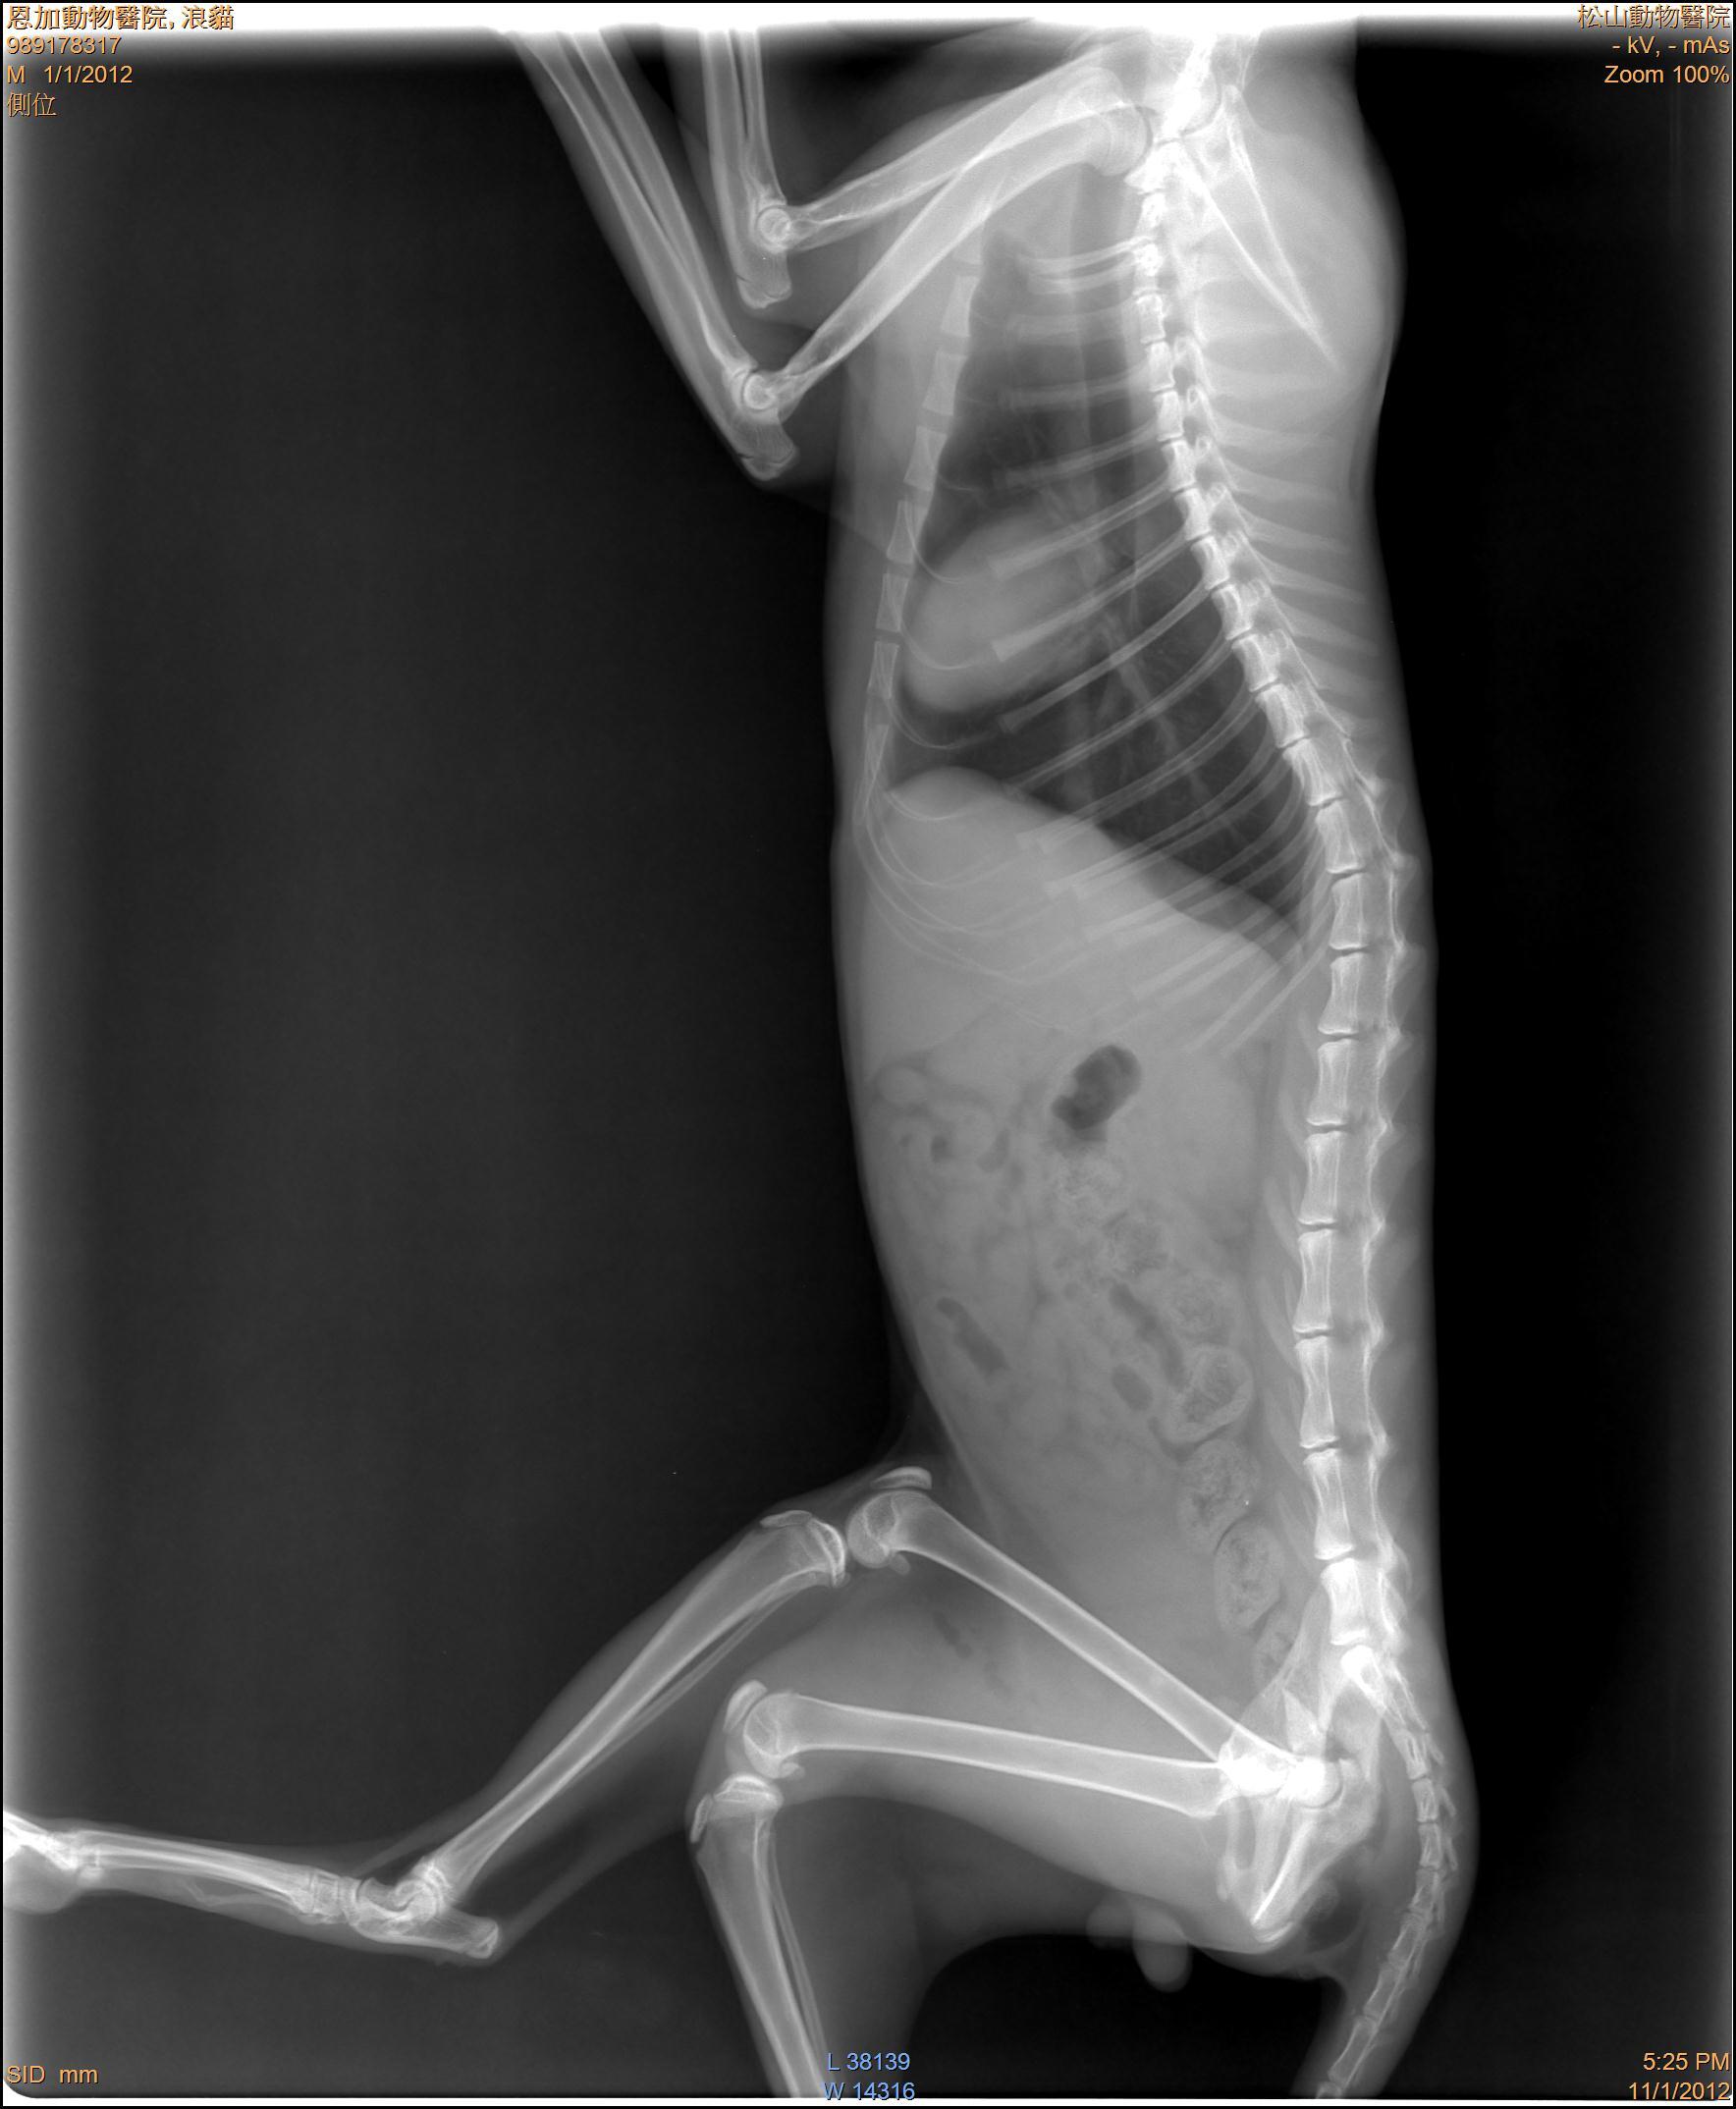

- 編號: 1467

主題: 骨盆受傷跛腳公貓 申請者姓名: 敏大哥 花色: 申請日期: 2012-11-24 16:50:51 申請者部落格: 申請者臉書網址: 所在縣市/合作醫院: 台北市/恩加動物醫院 治療費用: 7100元 需求人數: 16人 已結案 (2013-06-27 14:10:45) 報名人員: Anita Lu、Cherry Hsu(已付款)、Freda Shen(已付款)、Huai-chie Chiue(已付款)、小心(已付款)、盈盈(已付款)、常音(已付款)、Issa Chang(已付款)、mina(已付款)、Dale Peng(已付款)、Coco Ho(已付款)、Edwin(已付款)、Sky(已付款)、Sky(已付款)、Sky(已付款)、Sky(已付款)、Sky(已付款)、 候補人員: 陳宏林、 動物病情說明: 貓友文凡通報到請支持流浪貓TNR粉絲團,此貓在萬華區華中橋端,由我去誘捕帶回醫療,醫生說骨盆有骨折,治療之後發現除了骨盆的問題,還有神經受損的問題因此痊癒後先帶回照顧,看看神經問題能恢復多少,能否恢復行動力。